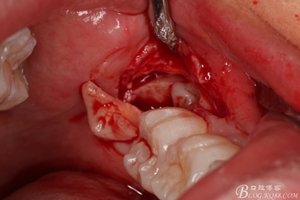

圖9.翻開瓣,可見38部分牙冠暴露

圖10. 翻開瓣。38牙冠還有部分骨質(zhì)覆蓋,遂用高速牙鉆去骨

圖11.去骨---暴露出38的牙冠最大周徑